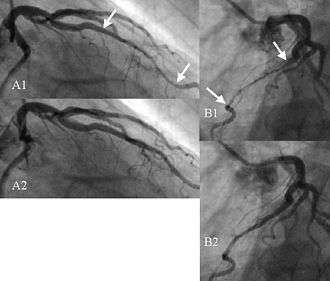

Figure 1 shows a series of angiographic images with a bridge on the left anterior descending coronary artery (LAD) in a male patient of 65 years.

- A1) Right anterior oblique view taken at end systole. The compressed vessel segment is indicated by the two arrows.

- B1) Left anterior oblique view taken nearly at the same instant.

- A2) Same view as in A1, but taken 133 ms later. The tunneled segment is no longer compressed.

- B2) Same view as in B1 but 133 ms later.